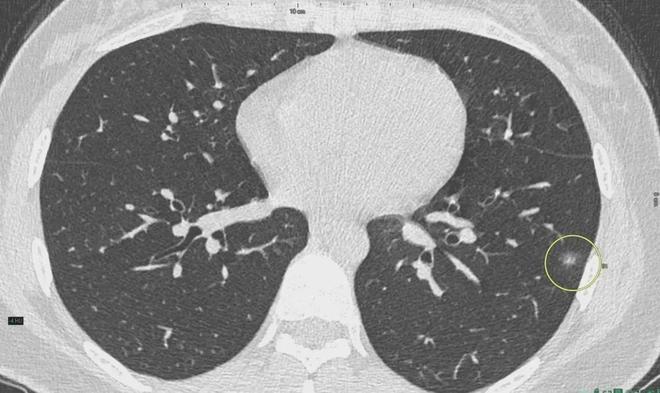

肺結(jié)節(jié)是一種常見的肺部疾病,其發(fā)病率逐年上升,雖然肺結(jié)節(jié)多數(shù)情況下是良性的,但也有可能惡化為肺癌,了解肺結(jié)節(jié)的形成原因?qū)τ陬A防和治療具有重要意義,本文將為您詳細解析肺結(jié)節(jié)的形成機制。

6、定期體檢:定期進行肺部檢查,及時發(fā)現(xiàn)并治療肺結(jié)節(jié)。

對于已經(jīng)發(fā)現(xiàn)肺結(jié)節(jié)的患者,應(yīng)及時就醫(yī),進行進一步的檢查和治療,醫(yī)生會根據(jù)患者的具體情況制定個性化的治療方案,包括藥物治療、手術(shù)治療等,早期發(fā)現(xiàn)、早期治療是提高肺結(jié)節(jié)治愈率的關(guān)鍵。